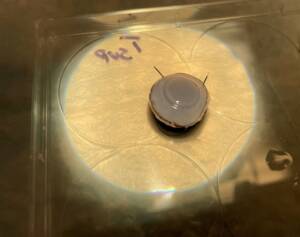

Photos of the Petri plates, 72 hours after bacterial (Streptococcus canis) inoculation.

The image and the inset show complete (positive) bacterial growth inhibition (full translucency)

at the treatment site after one dose of UV-C for 15 seconds at a 10 mm distance.

The blue lines divide the plate into quadrants.